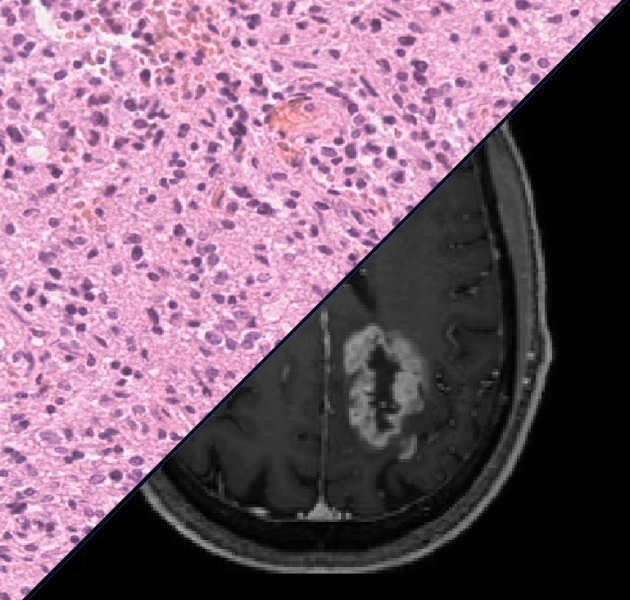

We are developing new machine learning tools to aid clinicians in diagnosing brain tumours through MRI and digital pathology.

Contact:

Matthew Grech-Sollars (m.grech-sollars@imperial.ac.uk)

We are investigating imaging biomarkers (diffusion MRI, perfusion MRI, MR Spectroscopy, choline PET) and developing the clinical tools needed to understand brain tumour growth and improve brain tumour diagnosis.